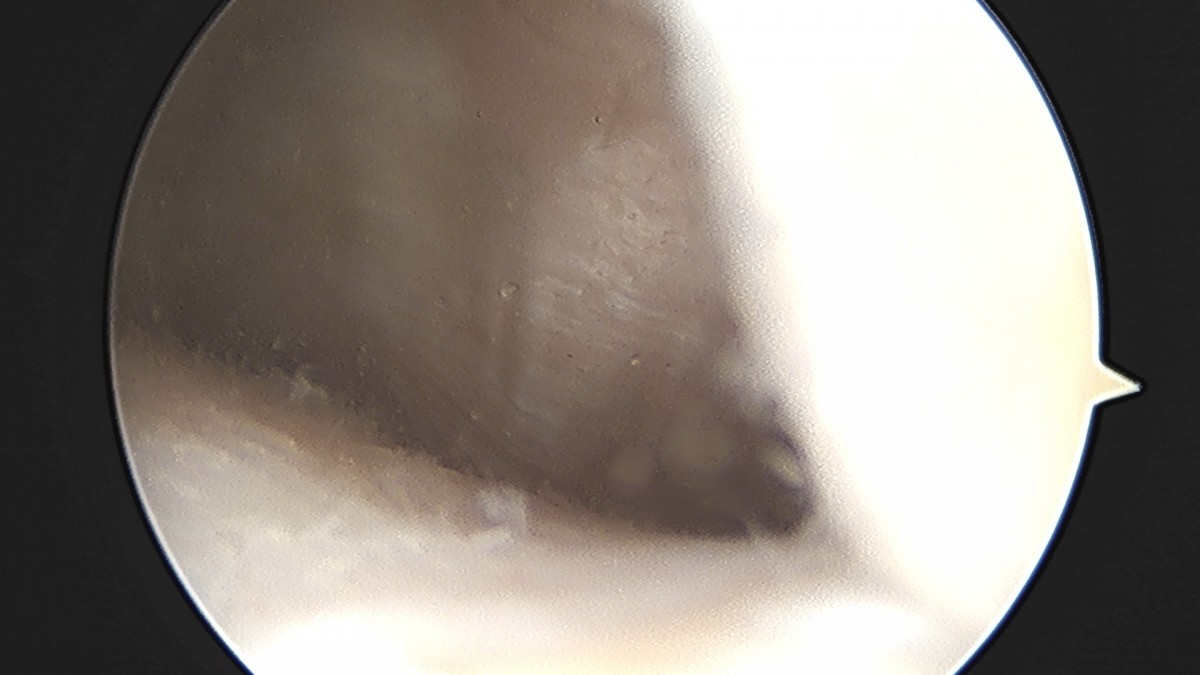

이재상원장님 무릎 반월상 연골판 절제술 이공O 환자

작성자 최고관리자 댓글 0건 조회 724회 작성일 25-09-16 15:43